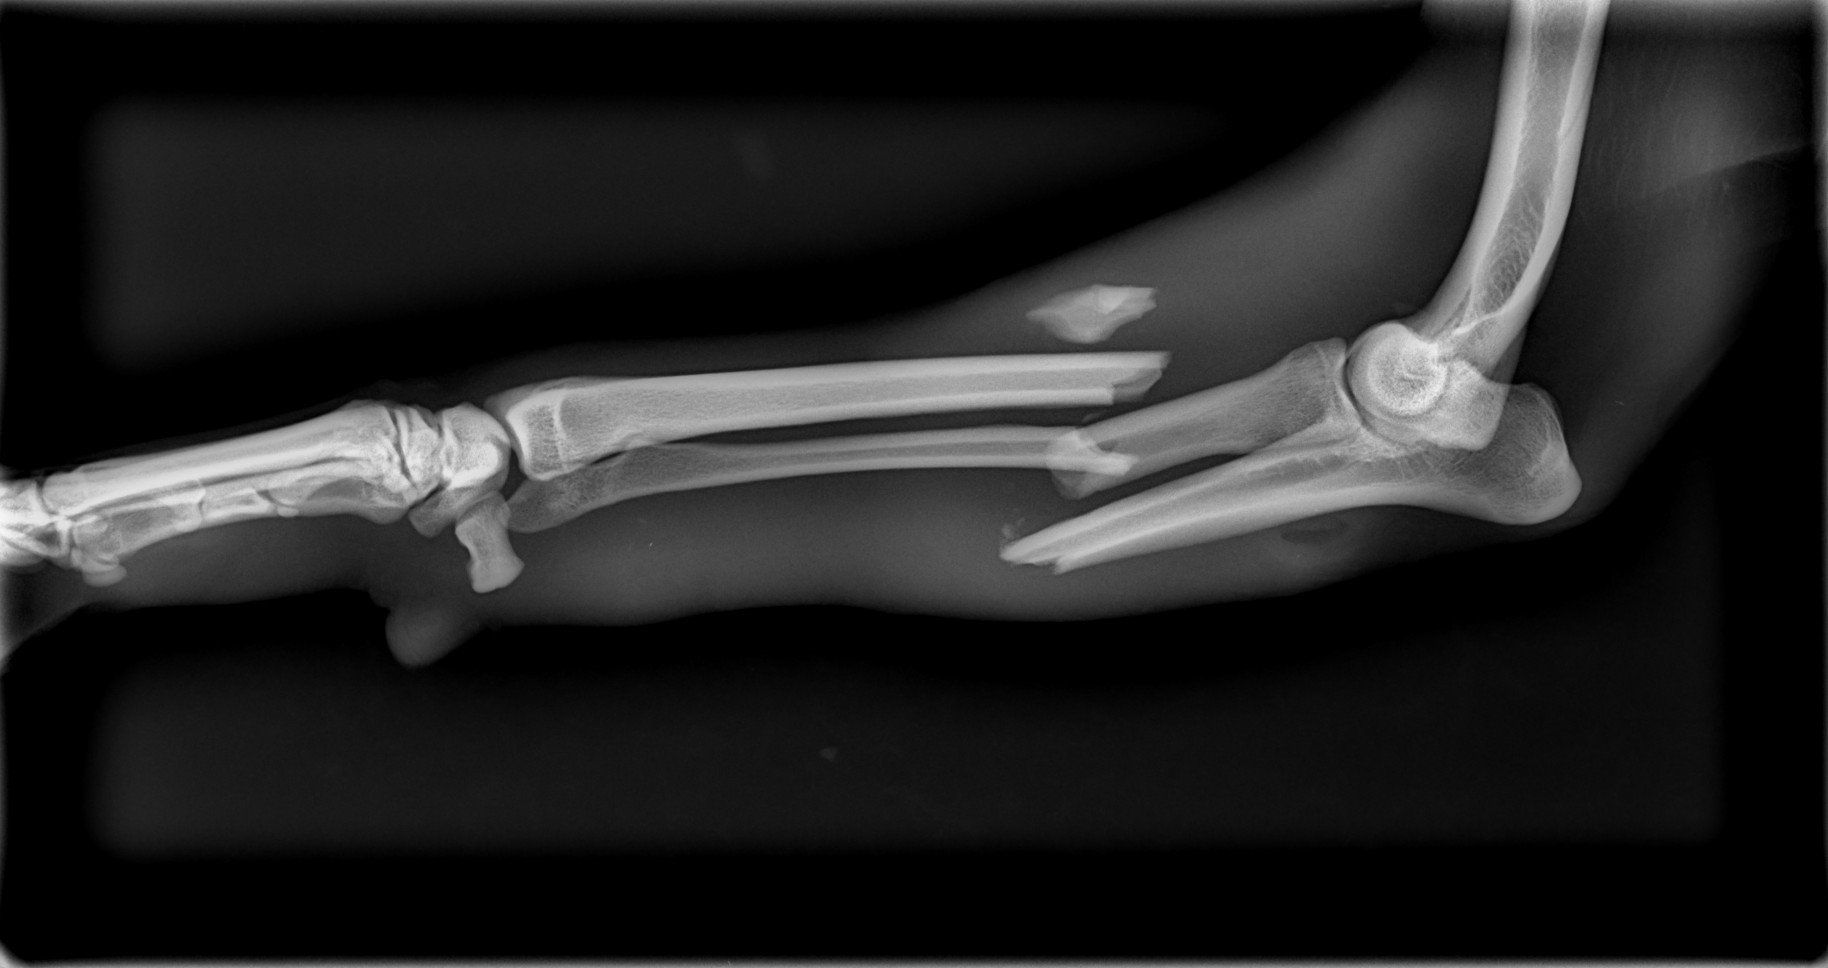

Sushy apareció atropellada en la carretera, de alli la llevaron a la perrera, donde querian sacrificarla, por suerte unas personas la sacaron y nos pidieron ayuda para ella, despues de traerla desde valencia ingreso en un hospital veterinario donde la operaron 3 veces, se paso varias semanas ingresada y cuando por fin salio a una casa de acogida se dio cuenta de que engordo en 3 dias y se le inflamaron las mamas.